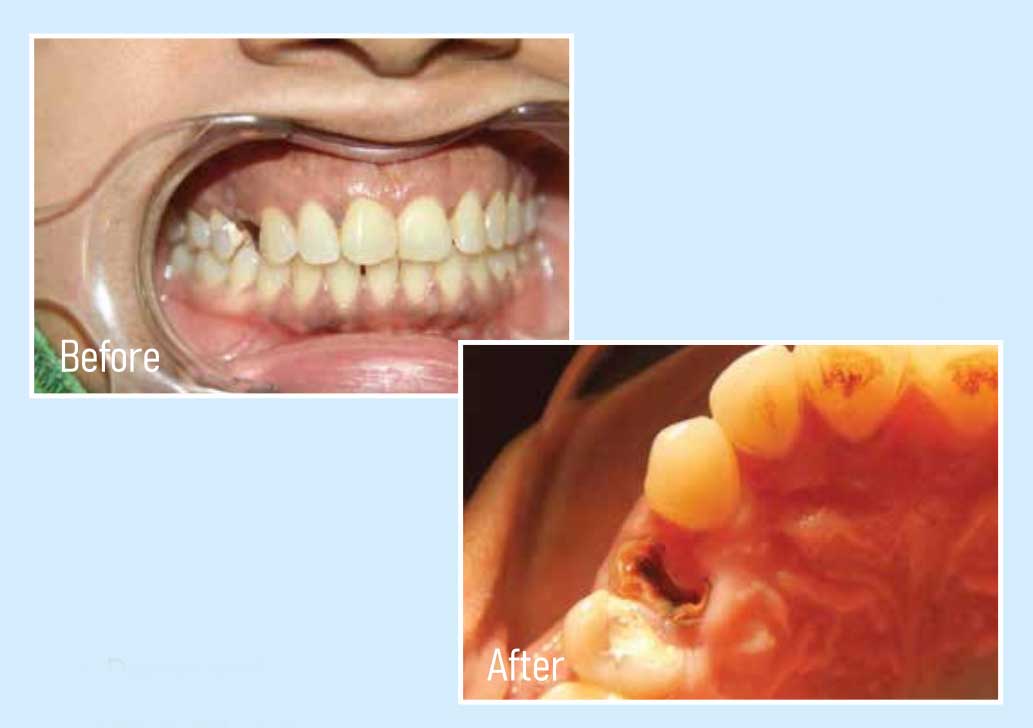

Dental implant is the perfect method and lifetime solution for replacing missing or badly damage tooth, absence of teeth for function and aesthetics. In absence of teeth human face in bite and chewing. Result in malnutrition and incomplete diagnosis. Only dental implants allow you to return the functionality of the tooth completely instead of natural teeth. With this you can enjoy your favorite Food like meat, nuts etc.

Instantly reverse age with missing teeth the face has a sunken appearance and a person looks much older than he/she on the actually with dental implant this is reverse immediately and a well-balanced natural and radiant smile is gained. This process alone would make one look at least 20 years youngest.

Successful replacement of teeth with implants is an extremely 'technique sensitive' process, requiring great expertise. An advanced titanium structure is anchored into the bone where the tooth is to be replaced. This structure acts like a support for the 'crown' or the artificial tooth. These mechanics are exactly similar to how a natural tooth anchors itself, and therefore, dental implants are the ideal replacement solution.